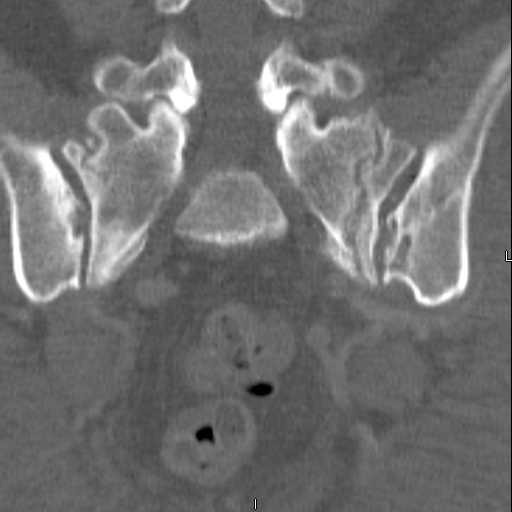

attached are images of a 59 yo female, admitted today after motor vehicle collision. Pt states her pelvis has been very painful ever since she fell on her buttocks from ground level a little over a year ago.

medical history significant for scleroderma, raynauds syndrome, and COPD. no past surgeries.

pt states she is very limited in walking ability secondary to pain. she requires a cane or a walker. friends and family do her shopping. the pain is localized primarily around left upper groin. she points to the rami region.

the question is if her medical history is contributing to the nonunions, and if anyone would consider surgical intervention, or is there some other successful intervention?